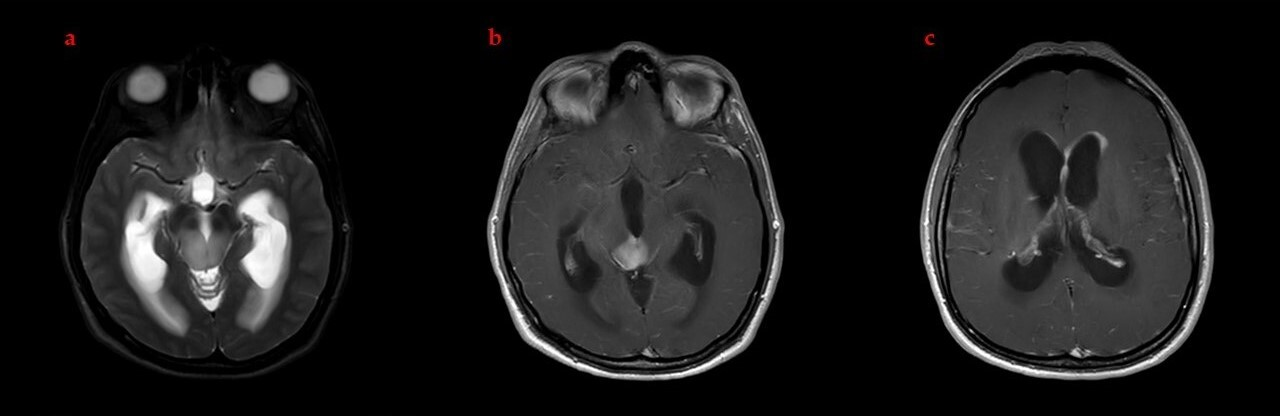

2.1. Clinical Presentation and Diagnosis